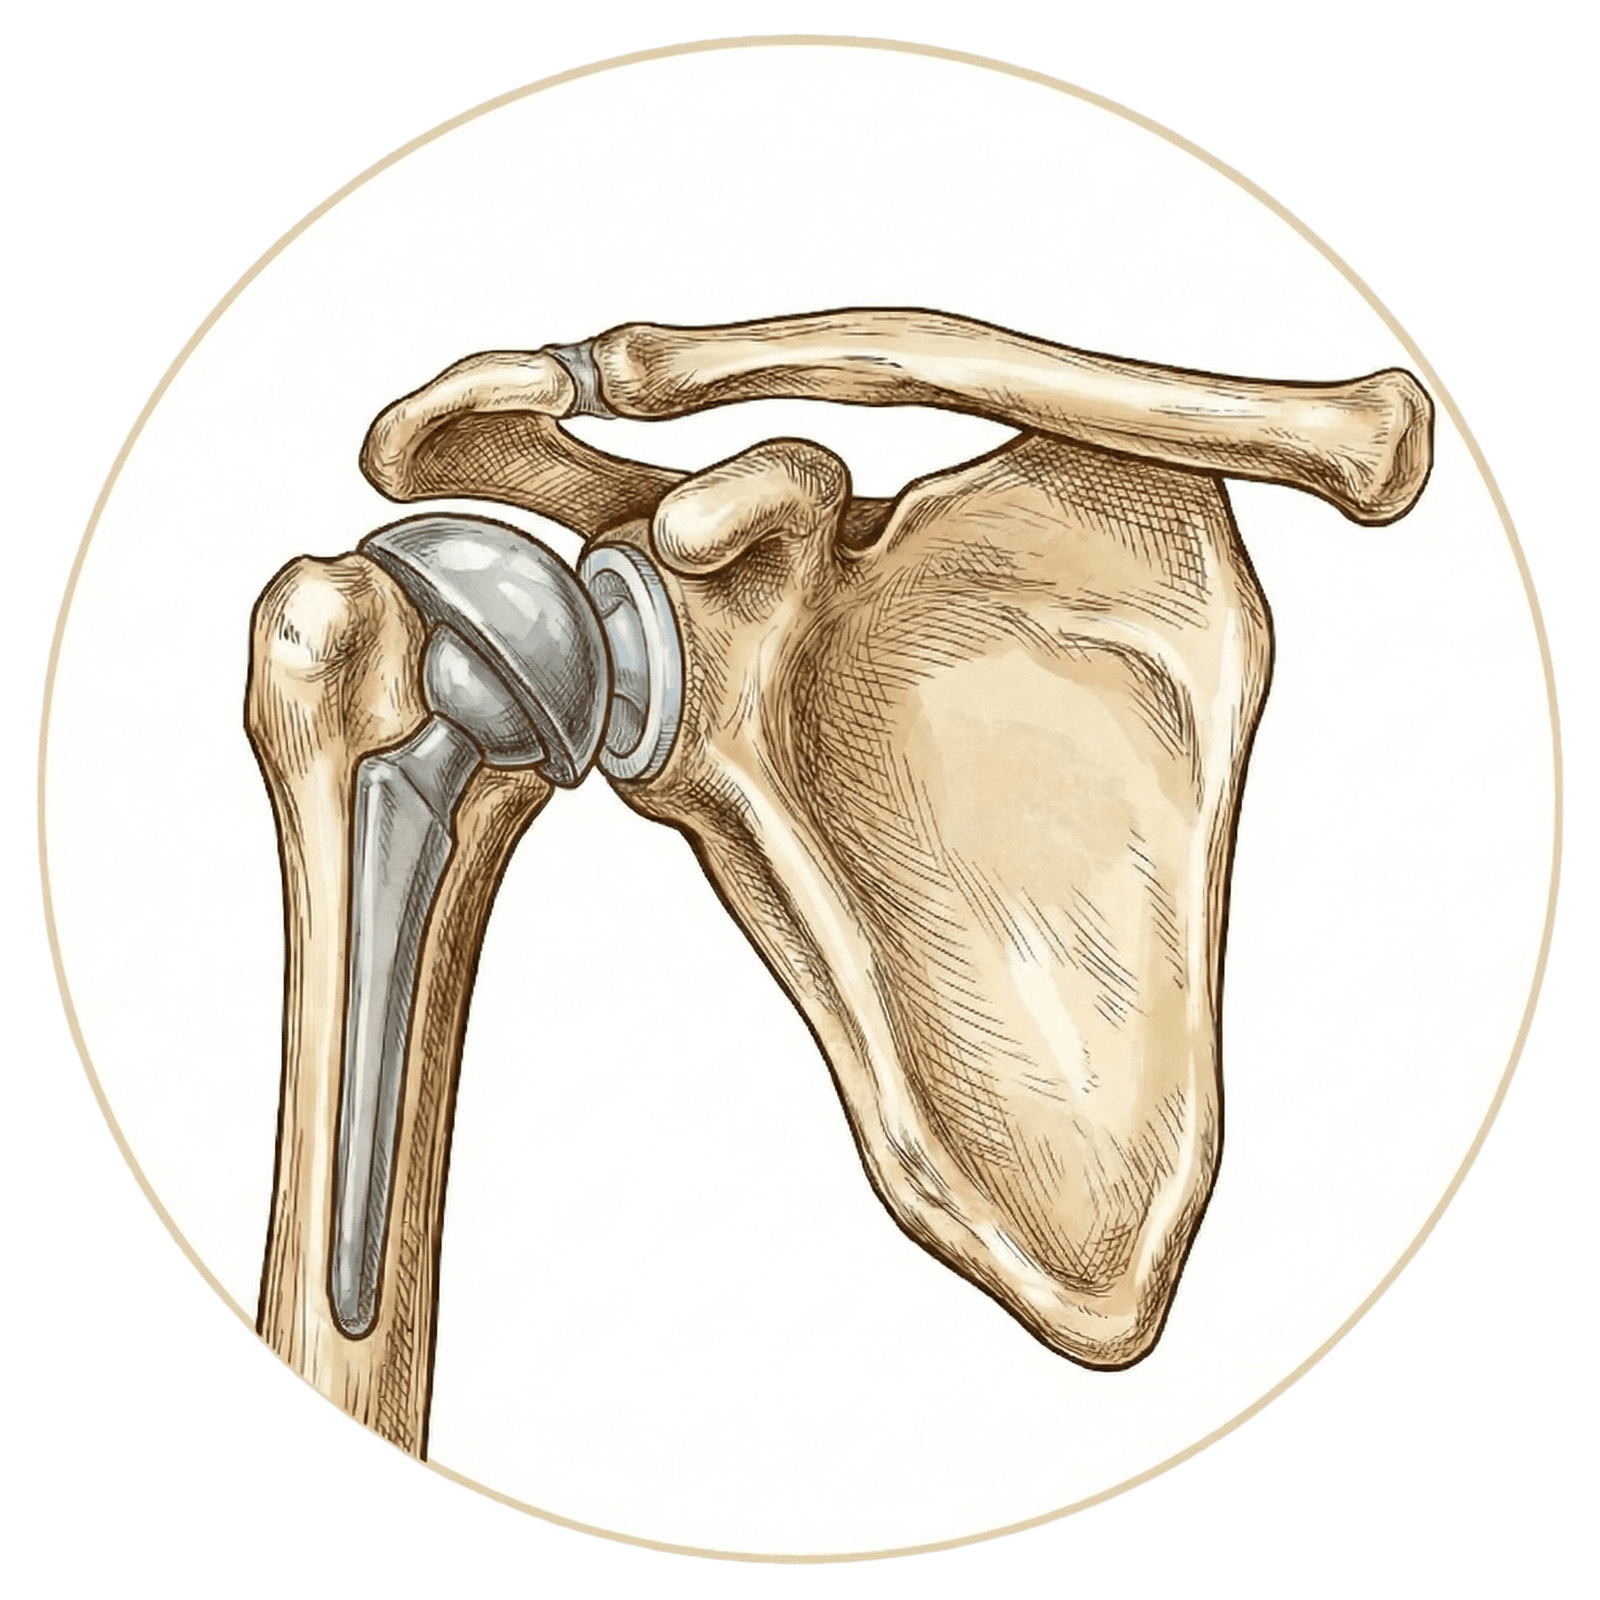

Protez

Diz Protezi

Kalça Protezi

Robotik Kalça Protezi

Dirsek Protezi